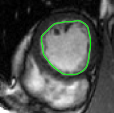

V-C LV and RV Segmentation: Quantitative Comparison to Commercial Software

Figures 8 and 9 shows some sample tracking results of the proposed method and Medviso on full cardiac cycles of two different cases on both the LV dataset and the RV dataset. The ground truth (yellow) is superimposed when available. A summary of the results on the entire datasets is shown in Table I. The accuracy with respect to ground truth is measured using average perpendicular distance (APD) and dice metric (DM) for left ventricle, and Hausdorff distance (HD) and DM for the right ventricle. These metrics are chosen since they are the standard ones used on these datasets. Both qualitative and quantitative results show that our proposed method leads to more accurate segmentation of the ventricles and thus leads to less interaction than segmentation propagation schemes in than Medviso.